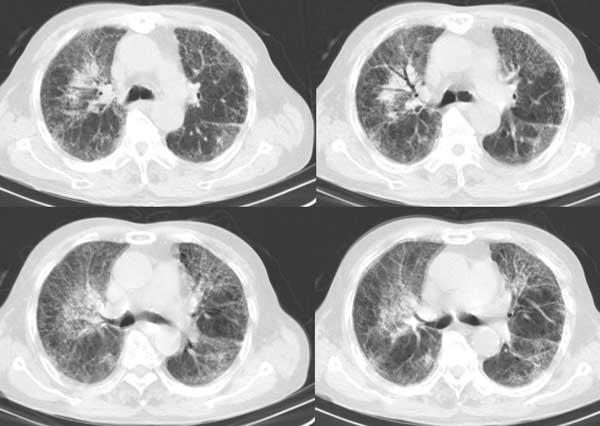

以下是引用同在2006-7-20 21:01:00的发言:[br]间质性肺炎,两肺纤维化,肺气肿。

以下是引用dalianren在2006-7-20 21:23:00的发言:[br]我考虑是肺泡蛋白沉积症:典型表现为两肺内散在片状\"磨玻璃\"样混浊区呈地图样分布.

以下是引用lj0804在2006-7-21 12:57:00的发言:[br]支持[br]我考虑是肺泡蛋白沉积症:典型表现为两肺内散在片状\"磨玻璃\"样混浊去呈地图样分布.